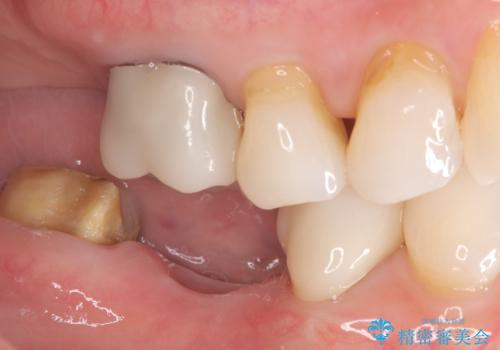

- 主訴:右下のセラミックのブリッジが何度も同じところで折れて壊れてしまう。

対合歯との咬合関係において、右下7番目と6番目の被せものの連結部がたわみやすい環境にあったため、ブリッジの新製ではなくインプラント治療を行いすべての歯を単冠仕上げとすることにしました。

何度も右下6、7間でブリッジが折れてしまうとのことでした。対合歯とブリッジの連結部が強く当たりたわみやすい状態でした。破折しずらい金属を使用したブリッジの選択もありましたが、支台歯(右下7)が失活歯場合、破折リスクが高く、破折してしまった場合にまたブリッジを外しての再治療になってしまう可能性を説明したところ、全て単冠仕上げとできるインプラント治療を希望されました。

右下5番のクラウンは、ブリッジを切断しそのまま使用していただいています。